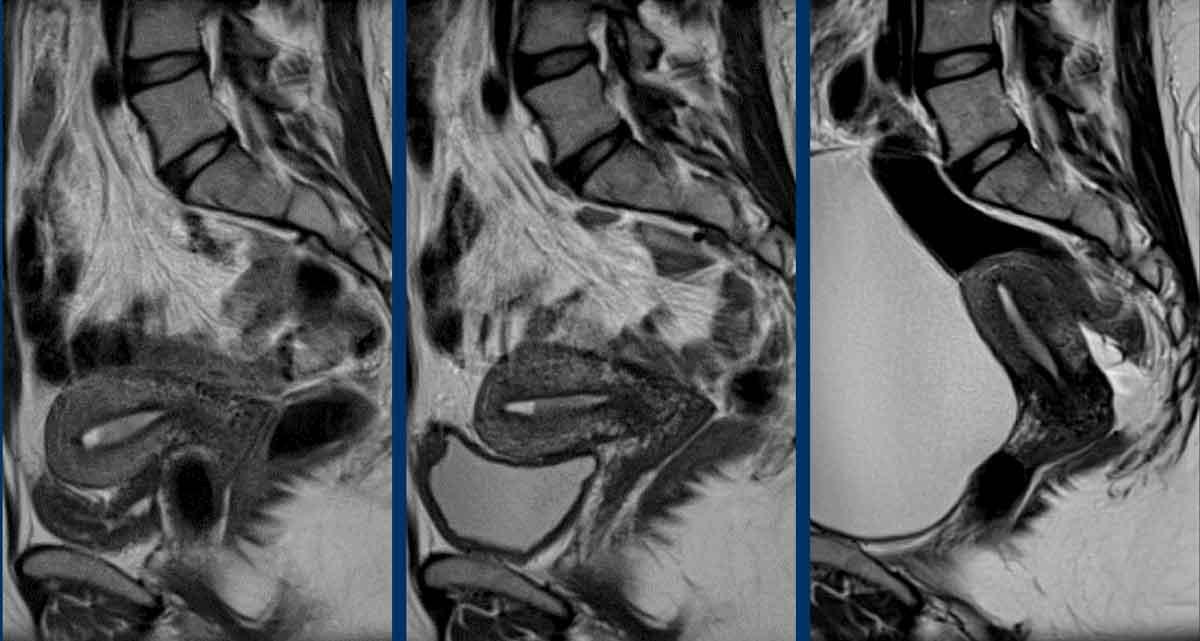

Đây là một ví dụ khác cho thấy cổ tử cung ở tư thế ngả sau và thân tử cung ở tư thế gập trước.

Hãy quan sát cách biến thể vị trí này ảnh hưởng đến việc lập kế hoạch chuỗi xung tương ứng.

Lưu ý: các biến thể trong vị trí tử cung

Cần lưu ý rằng vị trí của tử cung có thể thay đổi đáng kể giữa các lần chụp MRI và ngay cả trong quá trình chụp, phụ thuộc vào các yếu tố như mức độ đầy của bàng quang.

Những biến thể này, cũng như các biến thể về tư thế ngả và gập được mô tả ở trên, có thể là thách thức thực sự đối với kỹ thuật viên MRI.

Do đó, kỹ thuật viên MRI cần được đào tạo bài bản về cách nhận biết và xử lý các biến thể này.

Hơn nữa, khi kỹ thuật viên còn nghi ngờ, bác sĩ chẩn đoán hình ảnh cần có mặt trong quá trình chụp để giám sát và tư vấn, ví dụ như về việc làm rỗng bàng quang.